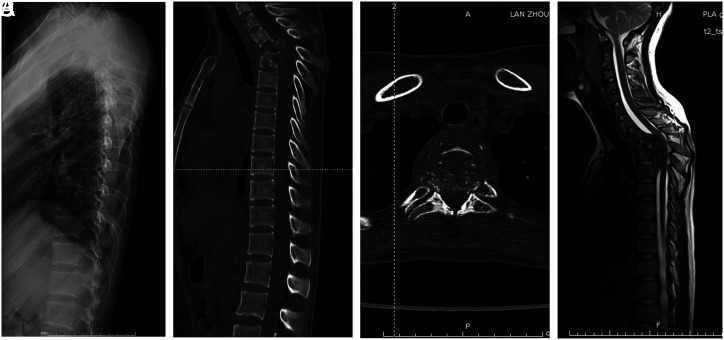

本研究旨在评估单纯后路清创、椎间融合和内固定术治疗上胸椎结核的有效性和可行性。本研究回顾性分析了 8 名确诊为上胸椎结核患者的临床和影像学数据。所有患者均接受了后路清创术、椎间融合术和内固定术。我们对视觉模拟量表(VAS)、Oswestry残疾指数(ODI)评分、红细胞沉降率(ESR)、C反应蛋白(CRP)、ASIA评分和椎体后凸Cobb角进行了术前和术后评估。背痛和下肢无力是最常见的症状。手术平均持续时间、失血量和术后引流量分别为 262.5 ± 43.3 分钟、625.0 ± 333.8 毫升和 285.0 ± 118.1 毫升。对患者进行了 36 至 48 个月的随访。术后三个月,VAS 和 ODI 评分明显改善,并在最后一次随访前进一步改善。术前和术后的差异有统计学意义(P < .05)。在最后的随访中,5 位瘫痪患者的下肢功能均已完全恢复正常。术后 3 个月内,血沉和 CRP 恢复正常,分别为 18.1 ± 7.3 mm/h 和 9.95 ± 5.41 mg/L。术前和术后存在统计学差异(P < .05)。平均畸形矫正率为 (71.5 ± 7.3)%,平均矫正角度损失为 (3.5 ± 1.4)°。所有患者均在术后 15 个月内(平均 8.3 ± 3.2 个月)实现了椎骨融合。单纯后路治疗上胸椎结核似乎是一种有效、安全、可靠的治疗方法,具有良好的临床和影像学效果。IV级,治疗性研究。

This study aimed to evaluate the effectiveness and feasibility of the posterior-only approach for debridement, interbody fusion, and internal fixation in treating upper thoracic tuberculosis. This study retrospectively analysed the clinical and radiographic data of 8 patients diagnosed with upper thoracic tuberculosis. All patients underwent posterior approach debridement, interbody fusion, and internal fixation. We conducted pre- and postoperative assessments of the visual analog scale (VAS), Oswestry disability index (ODI) scores, erythrocyte sedimentation rate (ESR), C-reactive protein (CRP), ASIA score, and kyphotic Cobb angle. Back pain and lower limb weakness were the most common presenting symptoms. The mean duration of surgery, amount of blood loss, and volume of postoperative drainage were 262.5 ± 43.3 min, 625.0 ± 333.8 mL, and 285.0 ± 118.1 mL, respectively. Patients were followed up for 36 to 48 months. Three months after surgery, there was a significant improvement in VAS and ODI scores, which further improved until the final follow-up. A statistically significant difference was observed between the preoperative and postoperative periods (P < .05). At the final follow-up, lower extremity function had fully returned to normal in all 5 paralyzed patients. The ESR and CRP returned to normal, 18.1 ± 7.3 mm/h and 9.95 ± 5.41 mg/L, respectively, within 3 months postoperatively. There were statistical differences between the preoperative and postoperative periods (P < .05). The average kyphotic correction rate was (71.5 ± 7.3)%, and the average loss of correction angle was (3.5 ± 1.4)°. Intervertebral bone fusion was achieved by all patients within 15 months (mean 8.3 ± 3.2 months) postoperatively. The posterior-only approach seems an effective, safe, and reliable treatment method for upper thoracic tuberculosis, with favourable clinical and radiological outcomes. Level IV, Therapeutic study.